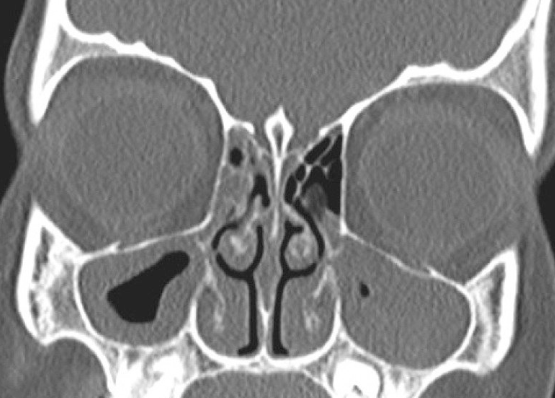

Imaging Tests

In some cases, imaging tests like X-rays or CT scans (Paranasal sinuses) may be ordered to obtain a detailed view of the sinuses. These tests can help identify any structural abnormalities or the presence of nasal polyps.